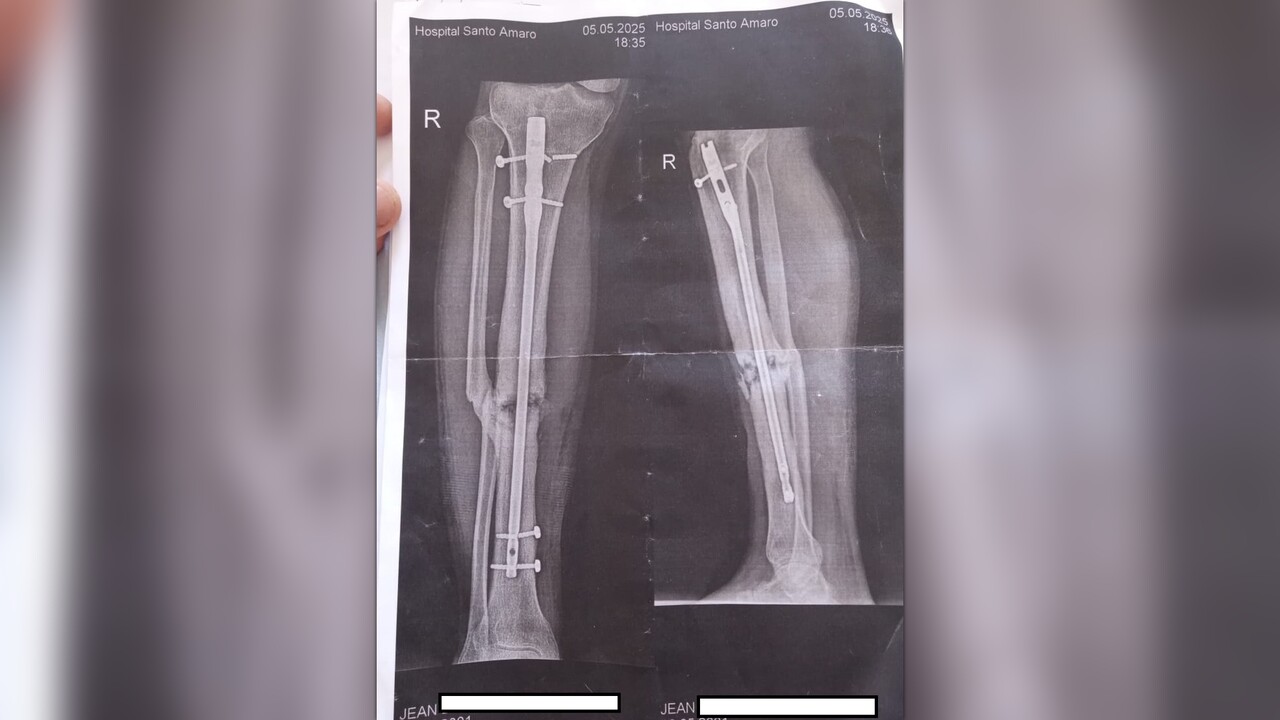

In 2023 I suffered a motorcycle accident that let me with multiple broken bones. Since then the bones didn't consolidate and I got osteomielitis which is an infecction in the bones. 4 surgeries total and going to the 5° one because of poor materials used in the surgeries.